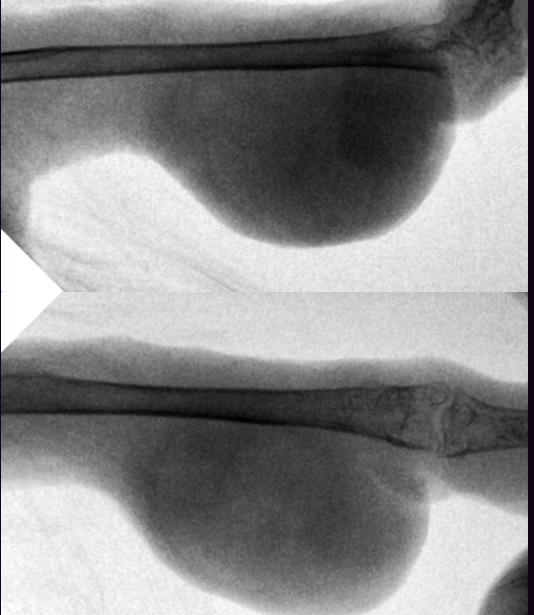

Zosia Опубликовано 30 января, 2020 #16 Опубликовано 30 января, 2020 Кость целая,без патологических изменений, без зон распада или абсцессов Броди. Возможно есть какие-то проблемы в суставе (кажется низковатой плотность, возможно след старой травмы СУСТАВА). Я сделала инверсию снимка, видится некое образование,кистоподобное, на латеральной проекции. Возможно исходит из суставной сумки (цифра 1). Это м.б. абсцессом, гигромой- но связано скорее всего с соедигнительной тканью. На склеродермию или подагрическое образование непохоже. На ВД проекции в нижней четверти кости есть (возможно это артефакт) некое нарушение четкой границы кости (цифра 2)... но параметры снимка не позволяют с уверенностью эту неровность оценить. Вопросы: Есть ли проблемы с дыханием Есть ли проблемы с пищеварением (рвота напрмиер) И нужен рентген "всей птицы", хотя бы один...

Zosia Опубликовано 1 февраля, 2020 #27 Опубликовано 1 февраля, 2020 На второй лапе- зона артроза или подагрических отложений (четкости никакой).

Dukemc Опубликовано 1 февраля, 2020 Автор #30 Опубликовано 1 февраля, 2020 На второй лапе был натоптыш, но появился после того, как опухоль начала интенсивнее рости и вследствие изменилась посадка птицы на жердочке. Он больше стал сидеть на здоровой стороне. Когда опухоль увеличелась еще больше(неделю назад) и он не смог цеплятся больной лапой за жердь и перешел на горизонтальнуюю поверхность. Изменилось положение тела, опираться стал на всю цевку и фаланги. Фаланги на больной лапе не двигаются и приподнятые вверх передние пальцы. За здоровую лапу сказать трудно, вроде пальцы двигаються и сгибаються но после разрастания опухоли суглоб на здоровой лапе стал толще (опухлее). По уклону передвигаеться сложно, при помощи клюва получается, натоптыш отпал. Опухоль изменила цвет.

Zosia Опубликовано 7 февраля, 2020 #35 Опубликовано 7 февраля, 2020 Рассмотриет возможность вскрытия образования (предположительно абсцесса) , у вас был вроде врач который об этом говорил. Обезболивание покровное (спреем). Вскрытие и очистка стандартные Недопустимо применение перекиси (у млеков при панарициях ее применяют) Извлеченный материал- по возможности- хотя бы на цитологию (а еще лучше на гисту). По второй лапе- с натоптышем- на форуме есть темы. Применять смеси (жидкие и порошкообразные). НПВС обязательно, С учетом крайней запущенности - имеет смысл в качестве НПВС взять даже Налгезин (напроксен), для того чтобы не было побочек с ЖКТ,т.к. предполагается очень длительное его использование. Доза допустима (максимальная суточная) 3 мг на 100 гр веса, в таком кол-ве- до 2 недель, далее снизить до 2 мг/100 гр веса.